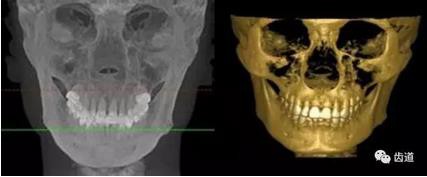

2、整形美容

整形美容假體測量應(yīng)用影像

五)口腔正畸

CBCT在頜骨正畸科方面的應(yīng)用:軟件功能的強(qiáng)大,提供有效的數(shù)據(jù),為頜骨正畸提供了極大的幫助,免除了很多臨床醫(yī)生的手工繪圖,并有利于科研、教學(xué)等方面發(fā)展研究。

投影測量側(cè)位片影像

軟件產(chǎn)生CEPH圖像注釋,不含X線射線圖像